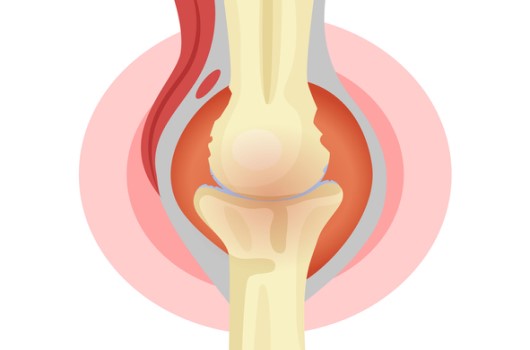

슬관절염은 슬관절의 연골 파괴와 염증으로 인해 발생하는 관절 질환으로, 통증, 염증, 강직성 등의 증상을 유발해요. 콘드로이친은 슬관절염 환자에서 통증 및 염증을 개선하는 데 도움이 돼요.

콘드로이친 효능은 연골 조직의 주요 구성 요소 중 한가지인 콘드로이틴 성분을 함유하고 있어요. 콘드로이친은 연골 조직의 재생과 보호에 기여하고, 슬관절의 염증을 줄이는 데도 효과가 있어요. 슬관절염 환자들이 콘드로이친을 복용하면, 연골 조직이 보호되어 연골 파괴가 줄어들고, 염증이 감소해서 슬관절 통증이 완화될 수 있어요.

콘드로이친은 관절세포를 재생시키는데 도움을 주고 외부 충격을 흡수, 개선시키는데에도 뛰어난 효과가 있어요. 그러나 콘드로이친은 노화가 진행되면서 수치가 점점 저하돼요. 이는 곧 연골의 뼈와 뼈사이의 완충효과 또는 보호기능 약화로 이어지는 것을 의미하기 때문에 나이가 들수록 콘드로이친을 보충해 주는 것이 좋아요.

콘드로이친은 연골을 재생 및 복구하고 무릎이 받는 충격과 스트레스를 흡수해서 연골을 보호할 수 있어요. 반대로 콘드로이친이 부족하게되면 연골은 수분 보유력과 탄력을 잃게 되고, 연골이 계속 마모되면서 뼈끼리 마찰을 일으켜 관절염을 유발하기 쉽기 때문인데요.